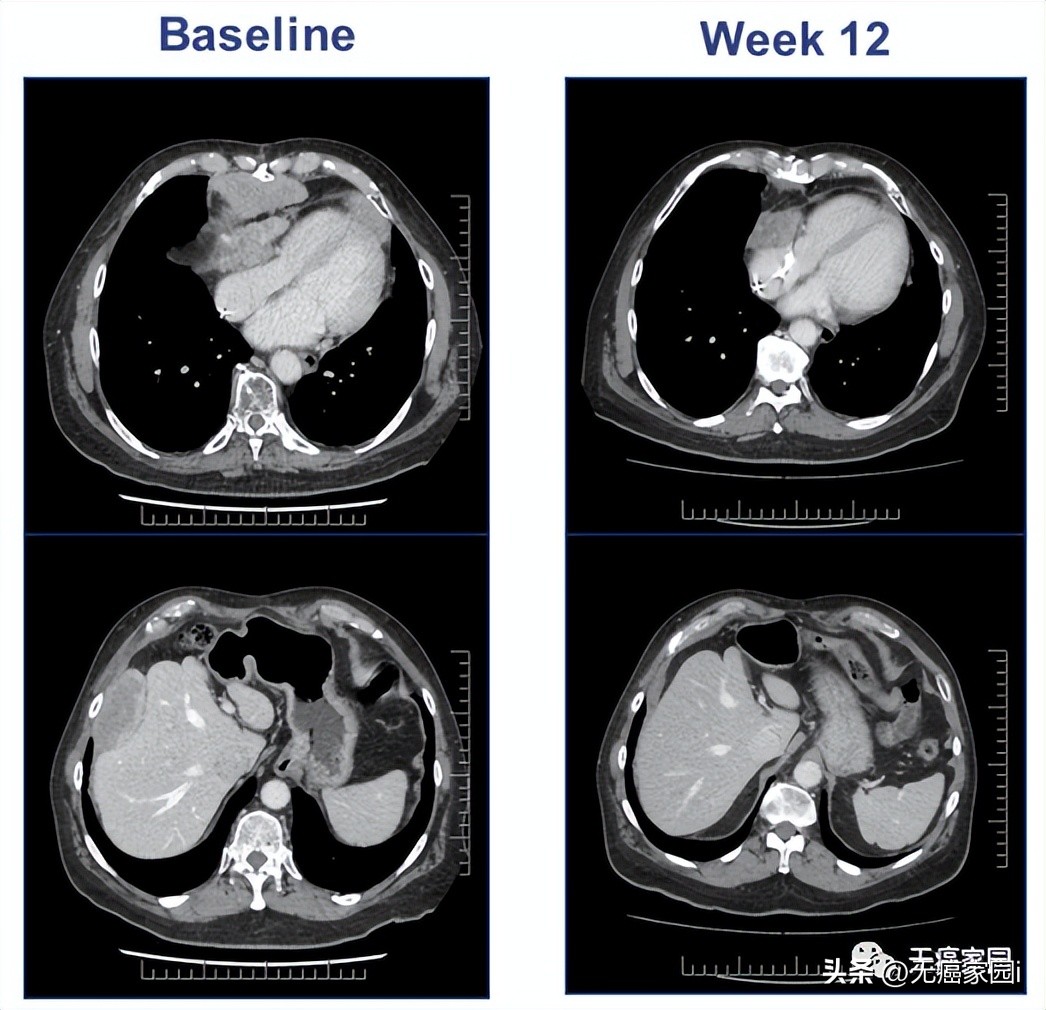

患者治疗前和治疗7个月后的CT结果

患者12为1名转移性宫颈癌患者,伴有胸壁、直肠和腹膜后转移(如图)。她之前曾接受过七种全身性抗癌药物治疗,包括基于 PD-1 的治疗。她经历了持续8个月的部分反应,三个疾病部位中的两个完全消退。完全消退的肿瘤在治疗后8个月仍未出现在影像学。